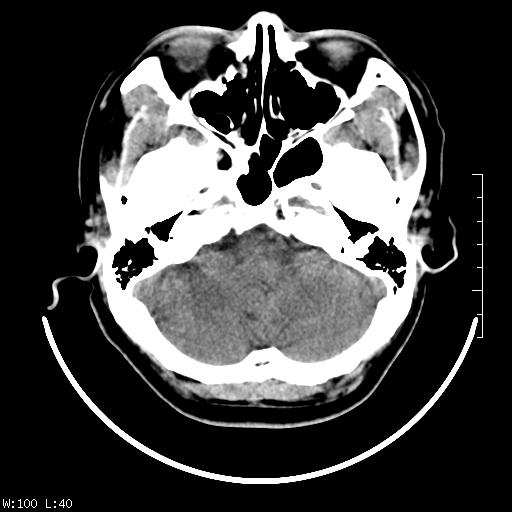

标题: CT22236:男,45,经常头痛。看看脑干正常吗? [打印本页]

标题: CT22236:男,45,经常头痛。看看脑干正常吗?

未见明显异常,建议ct增强或mri检查。

没见异常密度及形态改变啊,我认为是正常的。

颅脑ct轴位平扫颅内未见明确异常。

颅脑ct平扫未见明确异常,必要时mri检查。

颅脑ct平扫未见异常